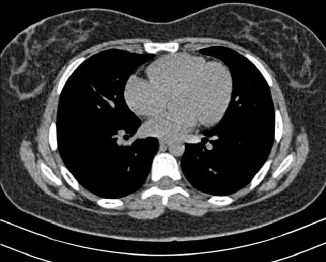

4.1.5 Chest CT

Chest CT scans play a relevant role in diagnosing a wide range of thoracic diseases, from infections to malignancies. By analyzing those scans, it is possible to detect diseases in the chest region, including pneumonia and cancer. The selected chest CT dataset 555https://www.kaggle.com/datasets/mohamedhanyyy/chest-ctscan-images contains 967 images across normal and three cancer types: adenocarcinoma, large-cell carcinoma, and squamous-cell carcinoma. Figure 6 provides a visual representation of the four highlighted classes.

Refer to caption

(a) Normal

(b) Adenocarcinoma

(c) Squamous cell carcinoma

(d) Large cell carcinoma

Figure 6: Chest CT scans.